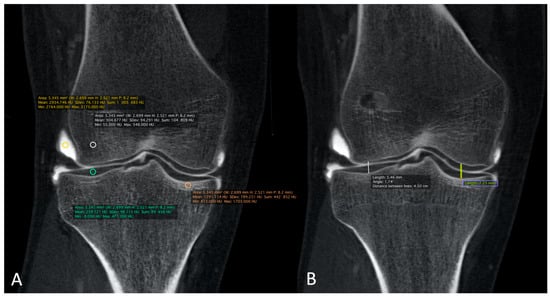

2.4. Quantitative Image Analysis of CBCT-A

The correspondence between electronic densities and the HU was evaluated using a standardized CIRS-062MA (Norkfold, VA, USA) phantom (Figure 3) for the CBCT images reconstructed with the two available reconstruction algorithms: MBIR 1 and MBIR2. The results were compared to the HU obtained from the two MDCT (SOMATOM Definition Flash Siemens Healthcare and Discovery 750 HD GE Healthcare) available in our department. The phantom comprises nine inserts with different materials corresponding to different electronic densities (Figure 3A). The reproducible region of interest (ROI) (size and seat) was placed in all nine inserts (Figure 3B), with three measurements for every item. Then, we analyzed the HU for all 32 CBCT-As in the coronal plane for the CM, trabecular subchondral bone, cortical bone, and cartilage densities after application of the MBIR2. ROIs were also placed in all cases, with three measurements for every item (Figure 4A). The mean was reported for statistical analysis.

Finally, MJWs were calculated, of the lateral and medial sides for the knee and center of the radio-carpal joint in the wrist or talocrural joint in the ankle, the tibio-talar joint in the ankle, and the femoro-tibial joint in the knee (Figure 4B), and compared with the corresponding DR images.

Table 4 summarizes the results obtained from the calibration of the HU with the standardized phantom. Measurements in both the MDCT (Siemens and GE) revealed similar densities in all tissues analyzed. For CBCT, the HU did not correspond to the usual values obtained for the MDCT, with a greater mean deviation obtained with the CT HU for the MBIR1 than for MBIR2. The mean HU calculated for the CBCT-A was 1966 for CM, 328 for trabecular bone, 812 for the subchondral cortex, and 330 for cartilage. We focused on bone density, as no normal values were found in the literature for cartilage; regarding CM, the contrast was diluted with the joint effusion in many cases. We noticed that the HU of CBCT-A measured for trabecular bone and cartilage were similar and corresponded to the bone density values of 200 mg/cc for the MDCT, with either MBIR1 or MBIR2 (236-298HU). The HU of subchondral cortical bone based on CBCT-A was similar to the HU of bone with a density of 80 mg/cc based on MDCT, particularly with MBIR2 (Table 4).

For CBCT, the HU did not correspond to the usual values obtained for the MDCT, with a mean deviation from the CT HU larger with the MBIR1 at −72% (SSD 221) than the MBIR2 at −52% (SSD 94). The current study is the first to compare these HU values between the MDCT and CBCT with two different iterative reconstruction algorithms: MBIR1 and MBIR2. The better results found with the MBIR2 were probably due to the device progress in the iterative reconstruction algorithm. Several studies have concluded that CBCT cannot be used for quantification purposes due to the poor calibration in the HU [18]. Swennen et al. stated that with CBCT, the “HU” of an organ’s voxel depends on the position in the image volume [31]. This means that DR attenuation of CBCT acquisition systems changes according to the position, producing different HU values for similar bony or soft tissue structures in different areas of the scanned volume. The partial gantry rotation causes an asymmetric dose distribution in the anatomical region of interest [21,32,33]. As seen in this study, the HUs were getting closer to the usual values obtained for the MDCT with MBIR2 as compared to MBIR1 (mean deviation from the CT HU of −72% for MBIR1 and −52% for MBIR2). Thus, we can expect that further improvements in cone-beam reconstruction algorithms and post-processing will reduce this drawback, permitting us to obtain HUs closer to those of the MDCT, thereby enabling quantitative measurements of some diseases, such as bone necrosis and osteopenia follow-ups.